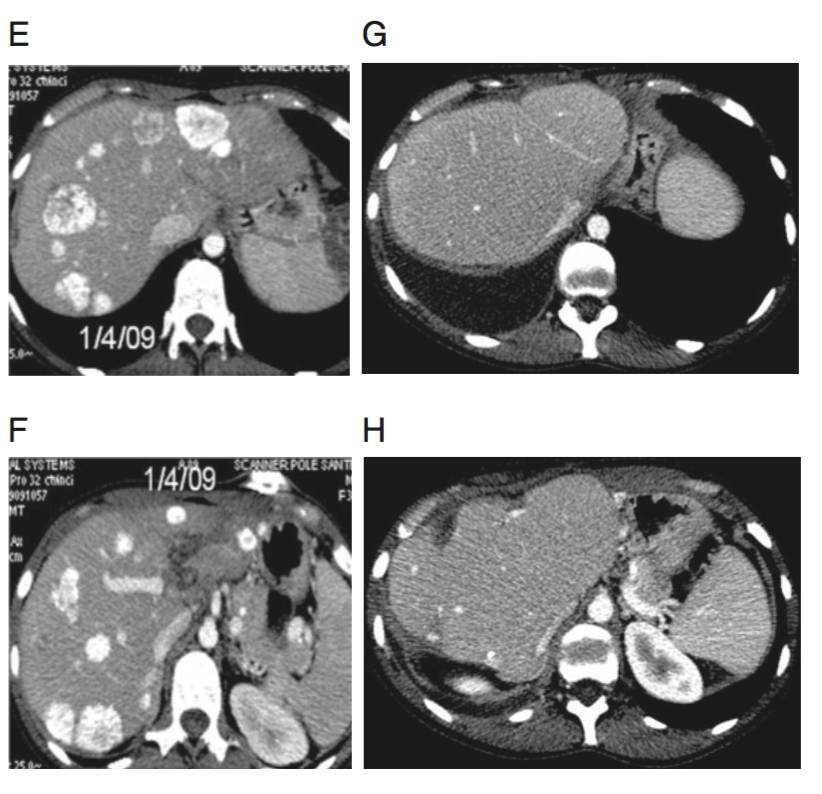

(A&B)上腹部CT显示多发、不可切除、同时性肝转移,原发灶来源自乙状结肠。

(C&D)在一线FOLFIRI方案9周期化疗后,复查CT评价为影像学略缓解(缩小幅度明显降低)。行乙状结肠癌切除术,术中留置HAI导管。

(E&F)4周期三药方案HAI+西妥昔单抗治疗后,复查CT评价为显著影像学缓解。行分期肝切除术。

(G&H)术后3年复查未见肿瘤复发,PS评分=0。